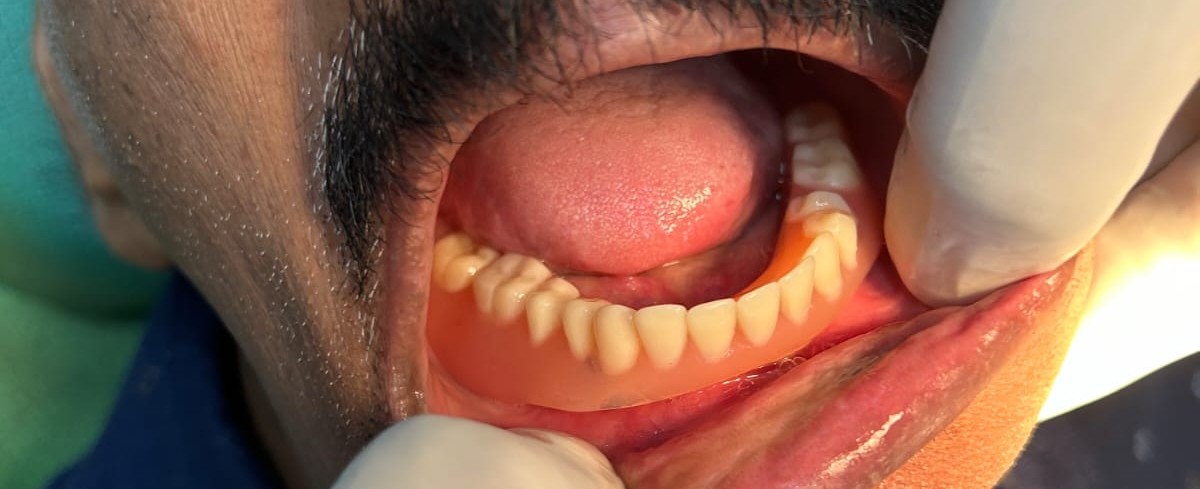

Dental implants are a modern and reliable solution for replacing missing teeth. They are designed to restore both the appearance and function of natural teeth. A dental implant consists of a small titanium post that is surgically placed into the jawbone, where it acts as an artificial root for the missing tooth. This procedure helps provide a stable and long-lasting foundation for the replacement tooth.

Dental implants are commonly recommended for patients who have lost one or more teeth due to injury, decay, or gum disease. Once the implant is placed into the jawbone, it gradually integrates with the bone through a natural healing process, providing strong support for the artificial tooth. After the healing period, a dental crown is attached to the implant to restore the appearance and function of the natural tooth. One of the major advantages of dental implants is that they help preserve the jawbone and prevent bone loss that can occur after tooth loss. Unlike removable dentures, implants are fixed in place and function similarly to natural teeth, allowing patients to chew, speak, and smile with confidence. With proper oral hygiene and regular dental check-ups, dental implants can last for many years. This treatment provides a durable and effective solution for restoring missing teeth and improving overall oral health and facial aesthetics.